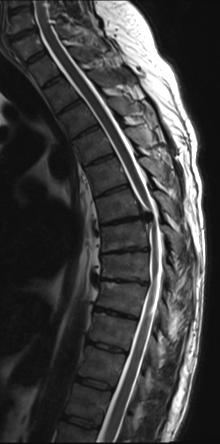

Unlike in the cervical and lumbar spine, pathology in the thoracic spine requiring surgery is not seen very often. Thoracic disc herniation (Figure 1) and stenosis are fairly uncommon with an estimated incidence of 1 case per 1,000,000 people.1 Patients may present with a variety of symptoms, such as back pain, radiculopathy, lower extremity weakness, urinary or bowel incontinence, and difficulty walking, which can make a correct diagnosis difficult.1–4 People with progressive myelopathic symptoms due to acute thoracic disc herniation or those with giant, heavily calcified herniations are often strongly recommended for surgery.1,2,5 Traditional surgical techniques, such as posterior decompression with instrumented fusion, anterior transthoracic approaches, or thoracoscopy are successful but carry with them significant rates of complications.1,6–8 In a systematic review, Court et al 1 found a significant rate of complications across several surgery techniques, including dural breach, worsening neurologic symptoms, intercostal neuralgia, and lung-related complications. A meta-analysis of 545 patients who underwent thoracoscopy for discectomy for thoracic herniation found that 24% experienced complications. This included pleural complications in 6% of cases and intercostal neuralgia in another 6% of cas -

Sagittal MRI of the thoracic spine showing disc herniation (arrow).

Source: Adapted from Corenman D. Herniated disc thoracic spine. NeckandBack.com. https://neckandback.com/conditions/herniated-disc-thoracic-spine/ es. 9 In a review of 17 patients undergoing mini-thoracotomy for thoracic disc herniation, Roelz et al found that 23% of patients experienced neurological deterioration in the postoperative period.10 In many places, the aforementioned approaches are still used to

Figure 1